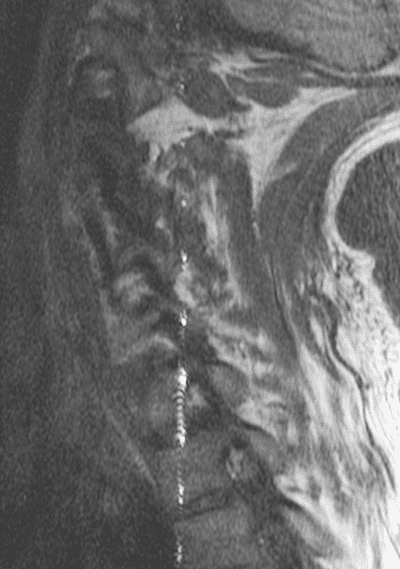

There is another RF-interference artifact in MRI, called [zipper-artifact][3], manifested on the clinical images is as a thin stripe up and down:

EzWjA.png

In the case of the zipper artifact there is a corruption of the signal sent back to the RF antenna from the patient being scanned, affecting a particular, specific frequency, which logically matches the polluting source. This frequency-specific phenomenon would affect each signal collected in the process of filling in k space. In contradistinction, a zipper artifact occurs at a single point in time, showing a dot in k-space.